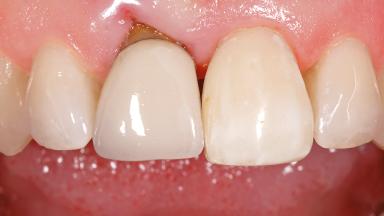

Early Placement of an Implant in a Maxillary Right Central Incisor Site

This 41-year-old female patient was referred to the clinic for the replacement of the right central incisor, since the tooth had developed a root fracture in the long axis that made extraction necessary. The healthy, non-smoking patient was first seen with the tooth still in place. A detailed Esthetic Risk Assessment was performed.The patient was worried about her dental esthetics and had high expectations for a successful treatment outcome from an esthetic point of view. The patient had a medium lip line that displayed parts of the gingiva in the anterior maxilla upon smile.